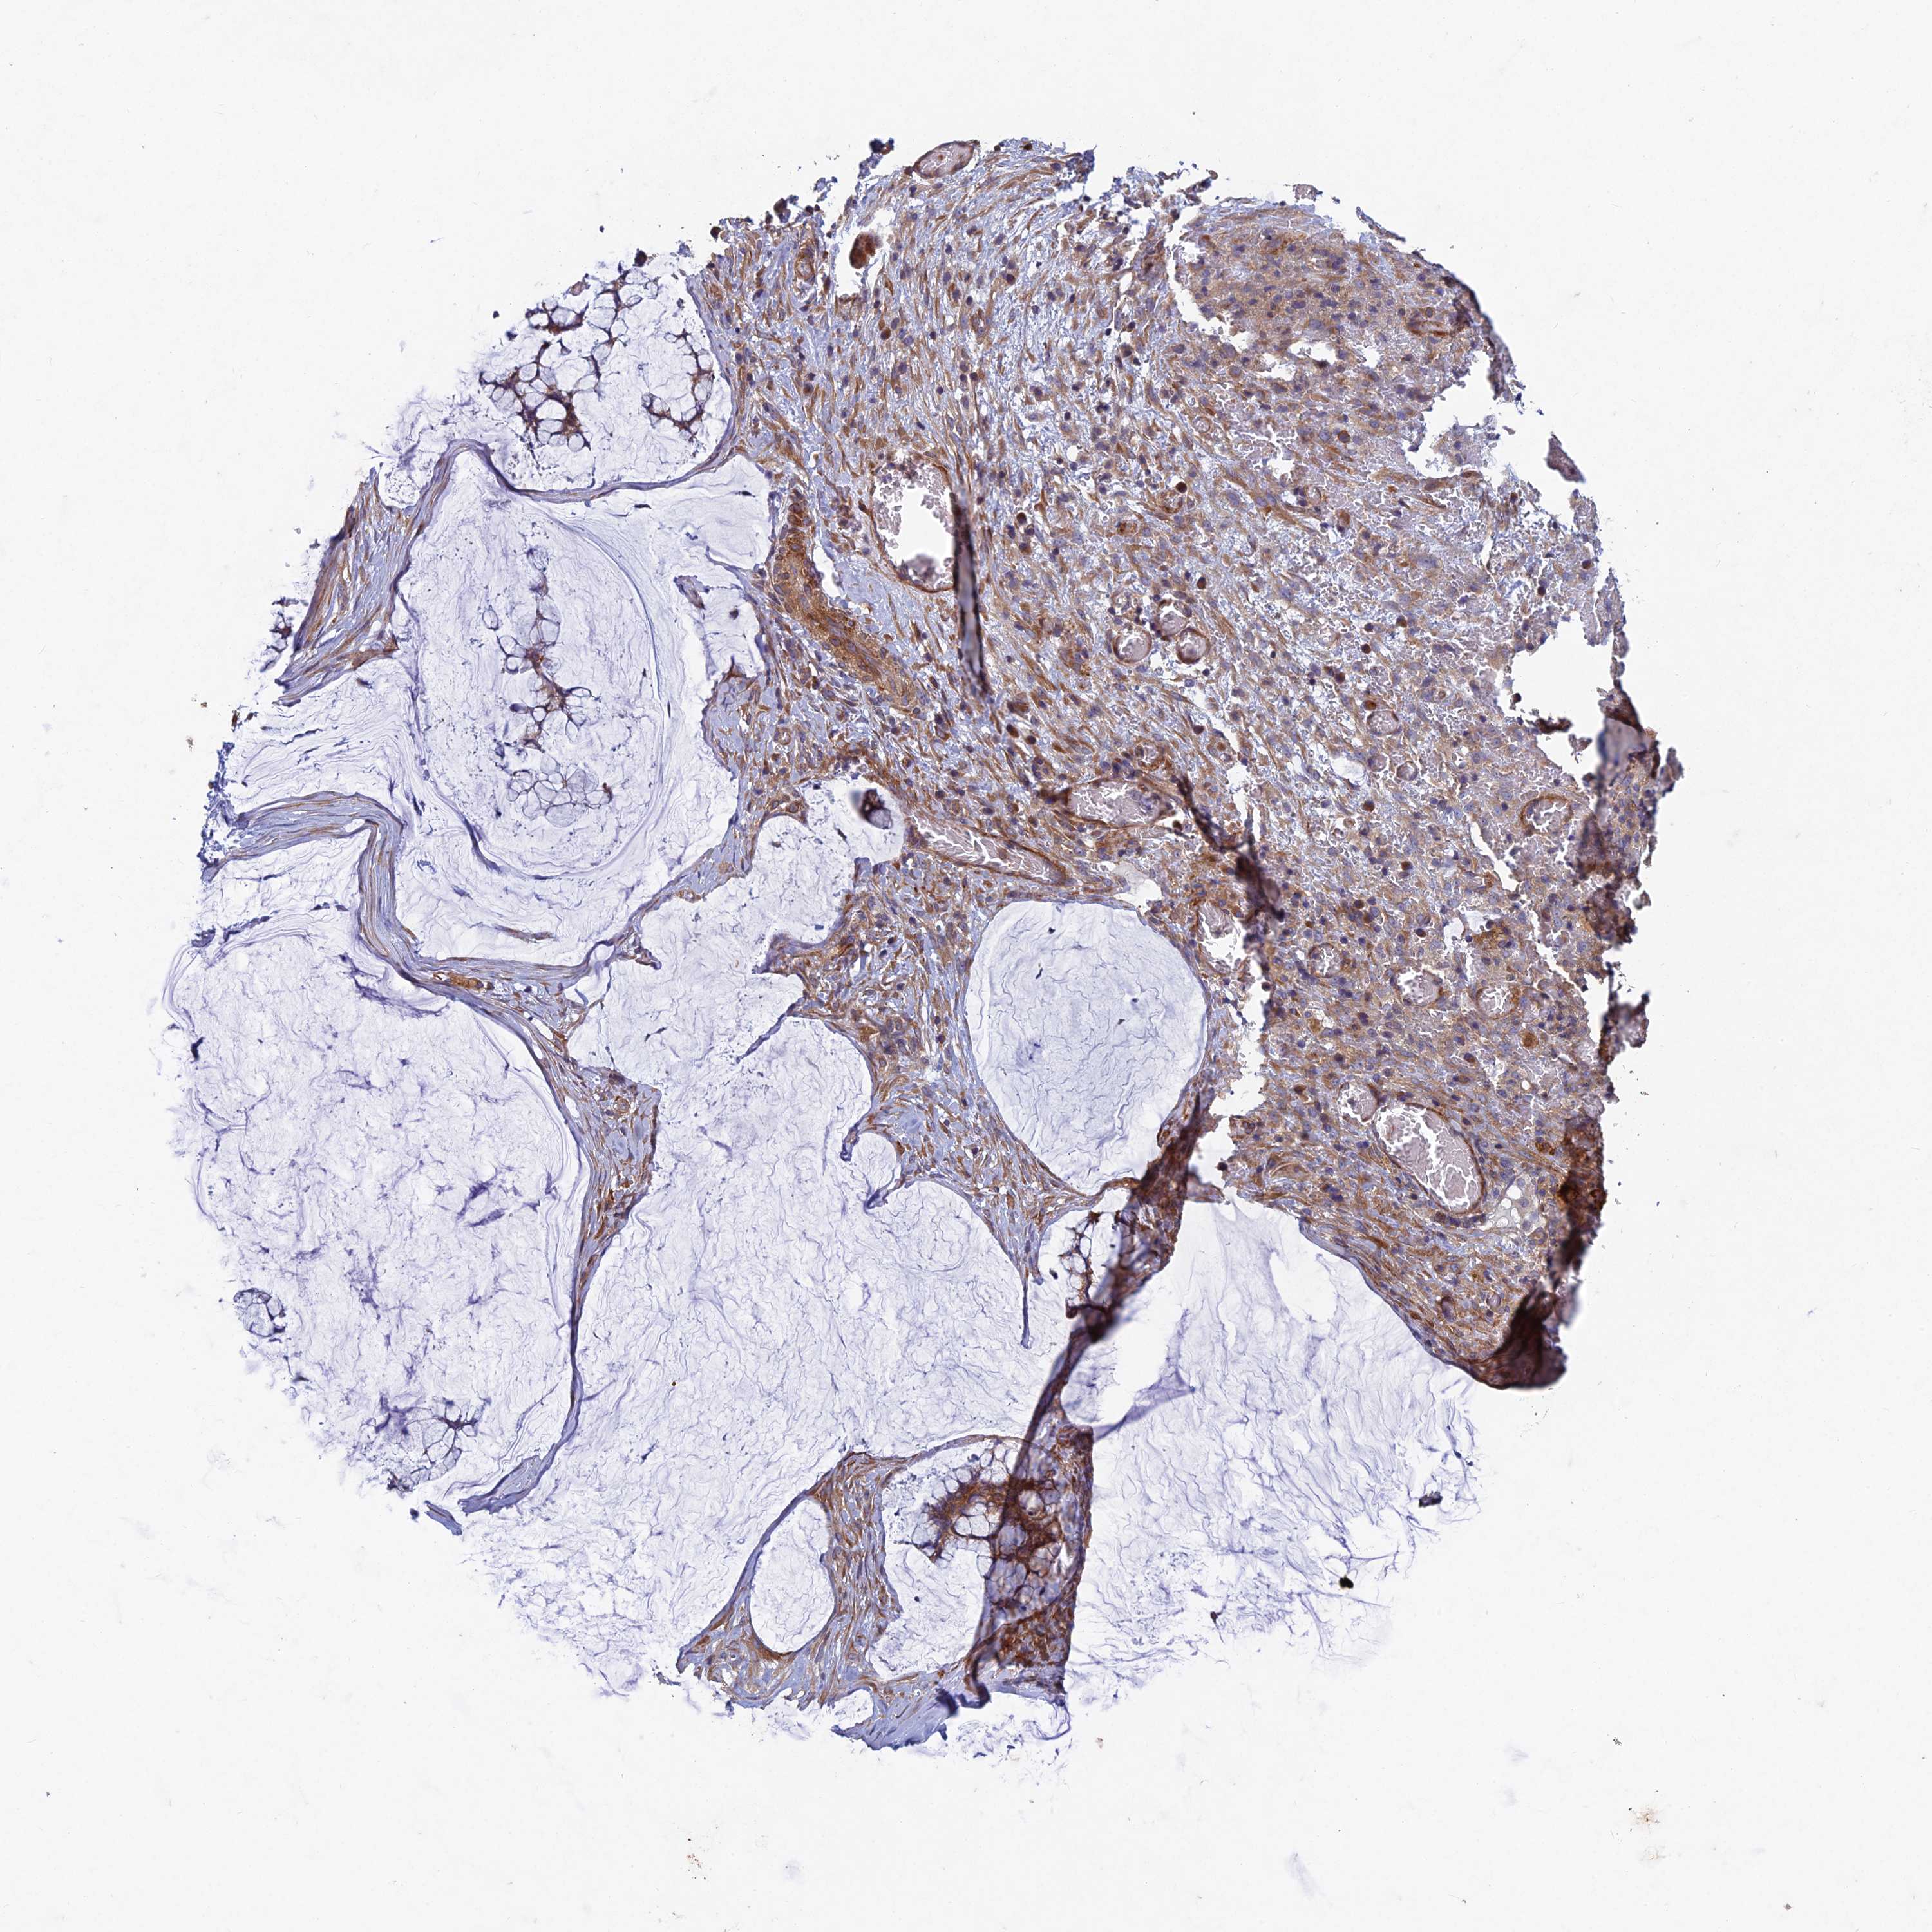

OVARIAN CANCER - Protein expressioni

A mouse-over function shows sample information and annotation data. Click on an image to view it in a full screen mode. Samples can be filtered based on level of antibody staining by selecting one or several of the following categories: high, medium, low and not detected. The assay and annotation is described here.

Note that samples used for immunohistochemistry by the Human Protein Atlas do not correspond to samples in the TCGA dataset.

Antibody stainingi

Antibody staining in the annotated cell types in the current human tissue is reported as not detected, low, medium, or high, based on conventional immunohistochemistry profiling in selected tissues. This score is based on the combination of the staining intensity and fraction of stained cells.

Each image is clickable and will lead to virtual microscopy that enables deeper exploration of all samples and also displays staining intensity scores, fraction scores and subcellular localization as well as patient and tissue information for each sample.

Antibody HPA039613

Staining

High

Medium

Low

Not detected

Intensity

Strong

Moderate

Weak

Negative

Quantity

>75%

75%-25%

<25%

None

Location

Nuclear

Cytoplasmic/membranous

Cytoplasmic/membranous,nuclear

Cystadenocarcinoma, serous, NOS

Carcinoma, endometroid

Cystadenocarcinoma, mucinous, NOS

Carcinoma, NOS